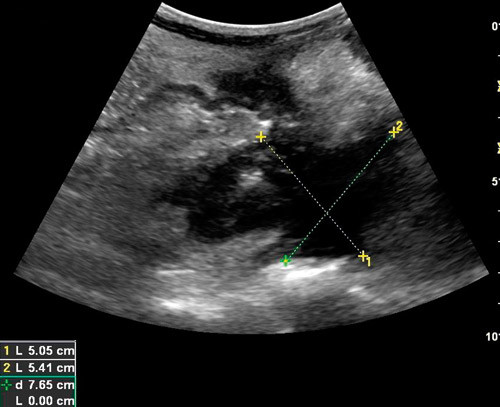

Intraabdominale abscesser er en annen kjent komplikasjon ved Crohns sykdom (fig 5). De oppstår vanligvis sekundært til fistulerende sykdom eller etter kirurgiske inngrep (21). Med ultralyd ser man hypoekkogene områder med uregelmessige avgrensninger. Små, hyperekkogene lesjoner kan noen ganger forekomme inne i abscesshuler på grunn av luft eller debris (12). Maconi og medarbeidere konkluderte i 2003 med at transabdominal ultralyd kan være et like godt førstevalg til å påvise fistler og abscesser ved Crohns sykdom som kontrastrøntgen eller CT (22). Fistler ble påvist med 71 % sensitivitet og 96 % spesifisitet, mens abscesser ble påvist med 81 % sensitivitet og 93 % spesifisitet. Våre erfaringer er at dype abscesser er best å visualisere med CT, mens overflatiske og små abscesser ses best med ultralyd.